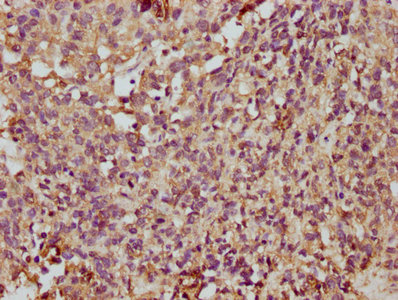

IHC image of PACO30486 diluted at 1:350 and staining in paraffin-embedded human pancreatic cancer performed on a Leica BondTM system. After dewaxing and hydration, antigen retrieval was mediated by high pressure in a citrate buffer (pH 6.0). Section was blocked with 10% normal goat serum 30min at RT. Then primary antibody (1% BSA) was incubated at 4°C overnight. The primary is detected by a biotinylated secondary antibody and visualized using an HRP conjugated SP system.

IHC image of PACO30486 diluted at 1:350 and staining in paraffin-embedded human ovarian cancer performed on a Leica BondTM system. After dewaxing and hydration, antigen retrieval was mediated by high pressure in a citrate buffer (pH 6.0). Section was blocked with 10% normal goat serum 30min at RT. Then primary antibody (1% BSA) was incubated at 4°C overnight. The primary is detected by a biotinylated secondary antibody and visualized using an HRP conjugated SP system.